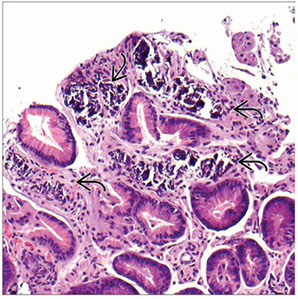

Figure 1: Gastric mucosal biopsies from children with autoimmune enteropathy often showed features of (a) chronic gastritis with increased lamina propria lymphoplasmacytic inflammation forming a superficial band within the mucous neck region. (b) In some cases, prominent intraepithelial lymphocytosis was identified within the surface, foveolar epithelium consistent with lymphocytic gastritis. (c) Concurrent autoimmune-related disorders were a common finding in patients with autoimmune enteropathy. Gastric biopsies taken from the fundus of case 14 demonstrated the features of autoimmune atrophic gastritis with partial parietal cell loss and superficial intestinal metaplasia. (d) In a subset of patients, multiple apoptotic bodies (arrows) were identified within the deep glandular mucosa.